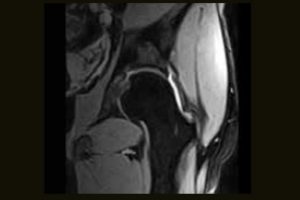

Clinical Images